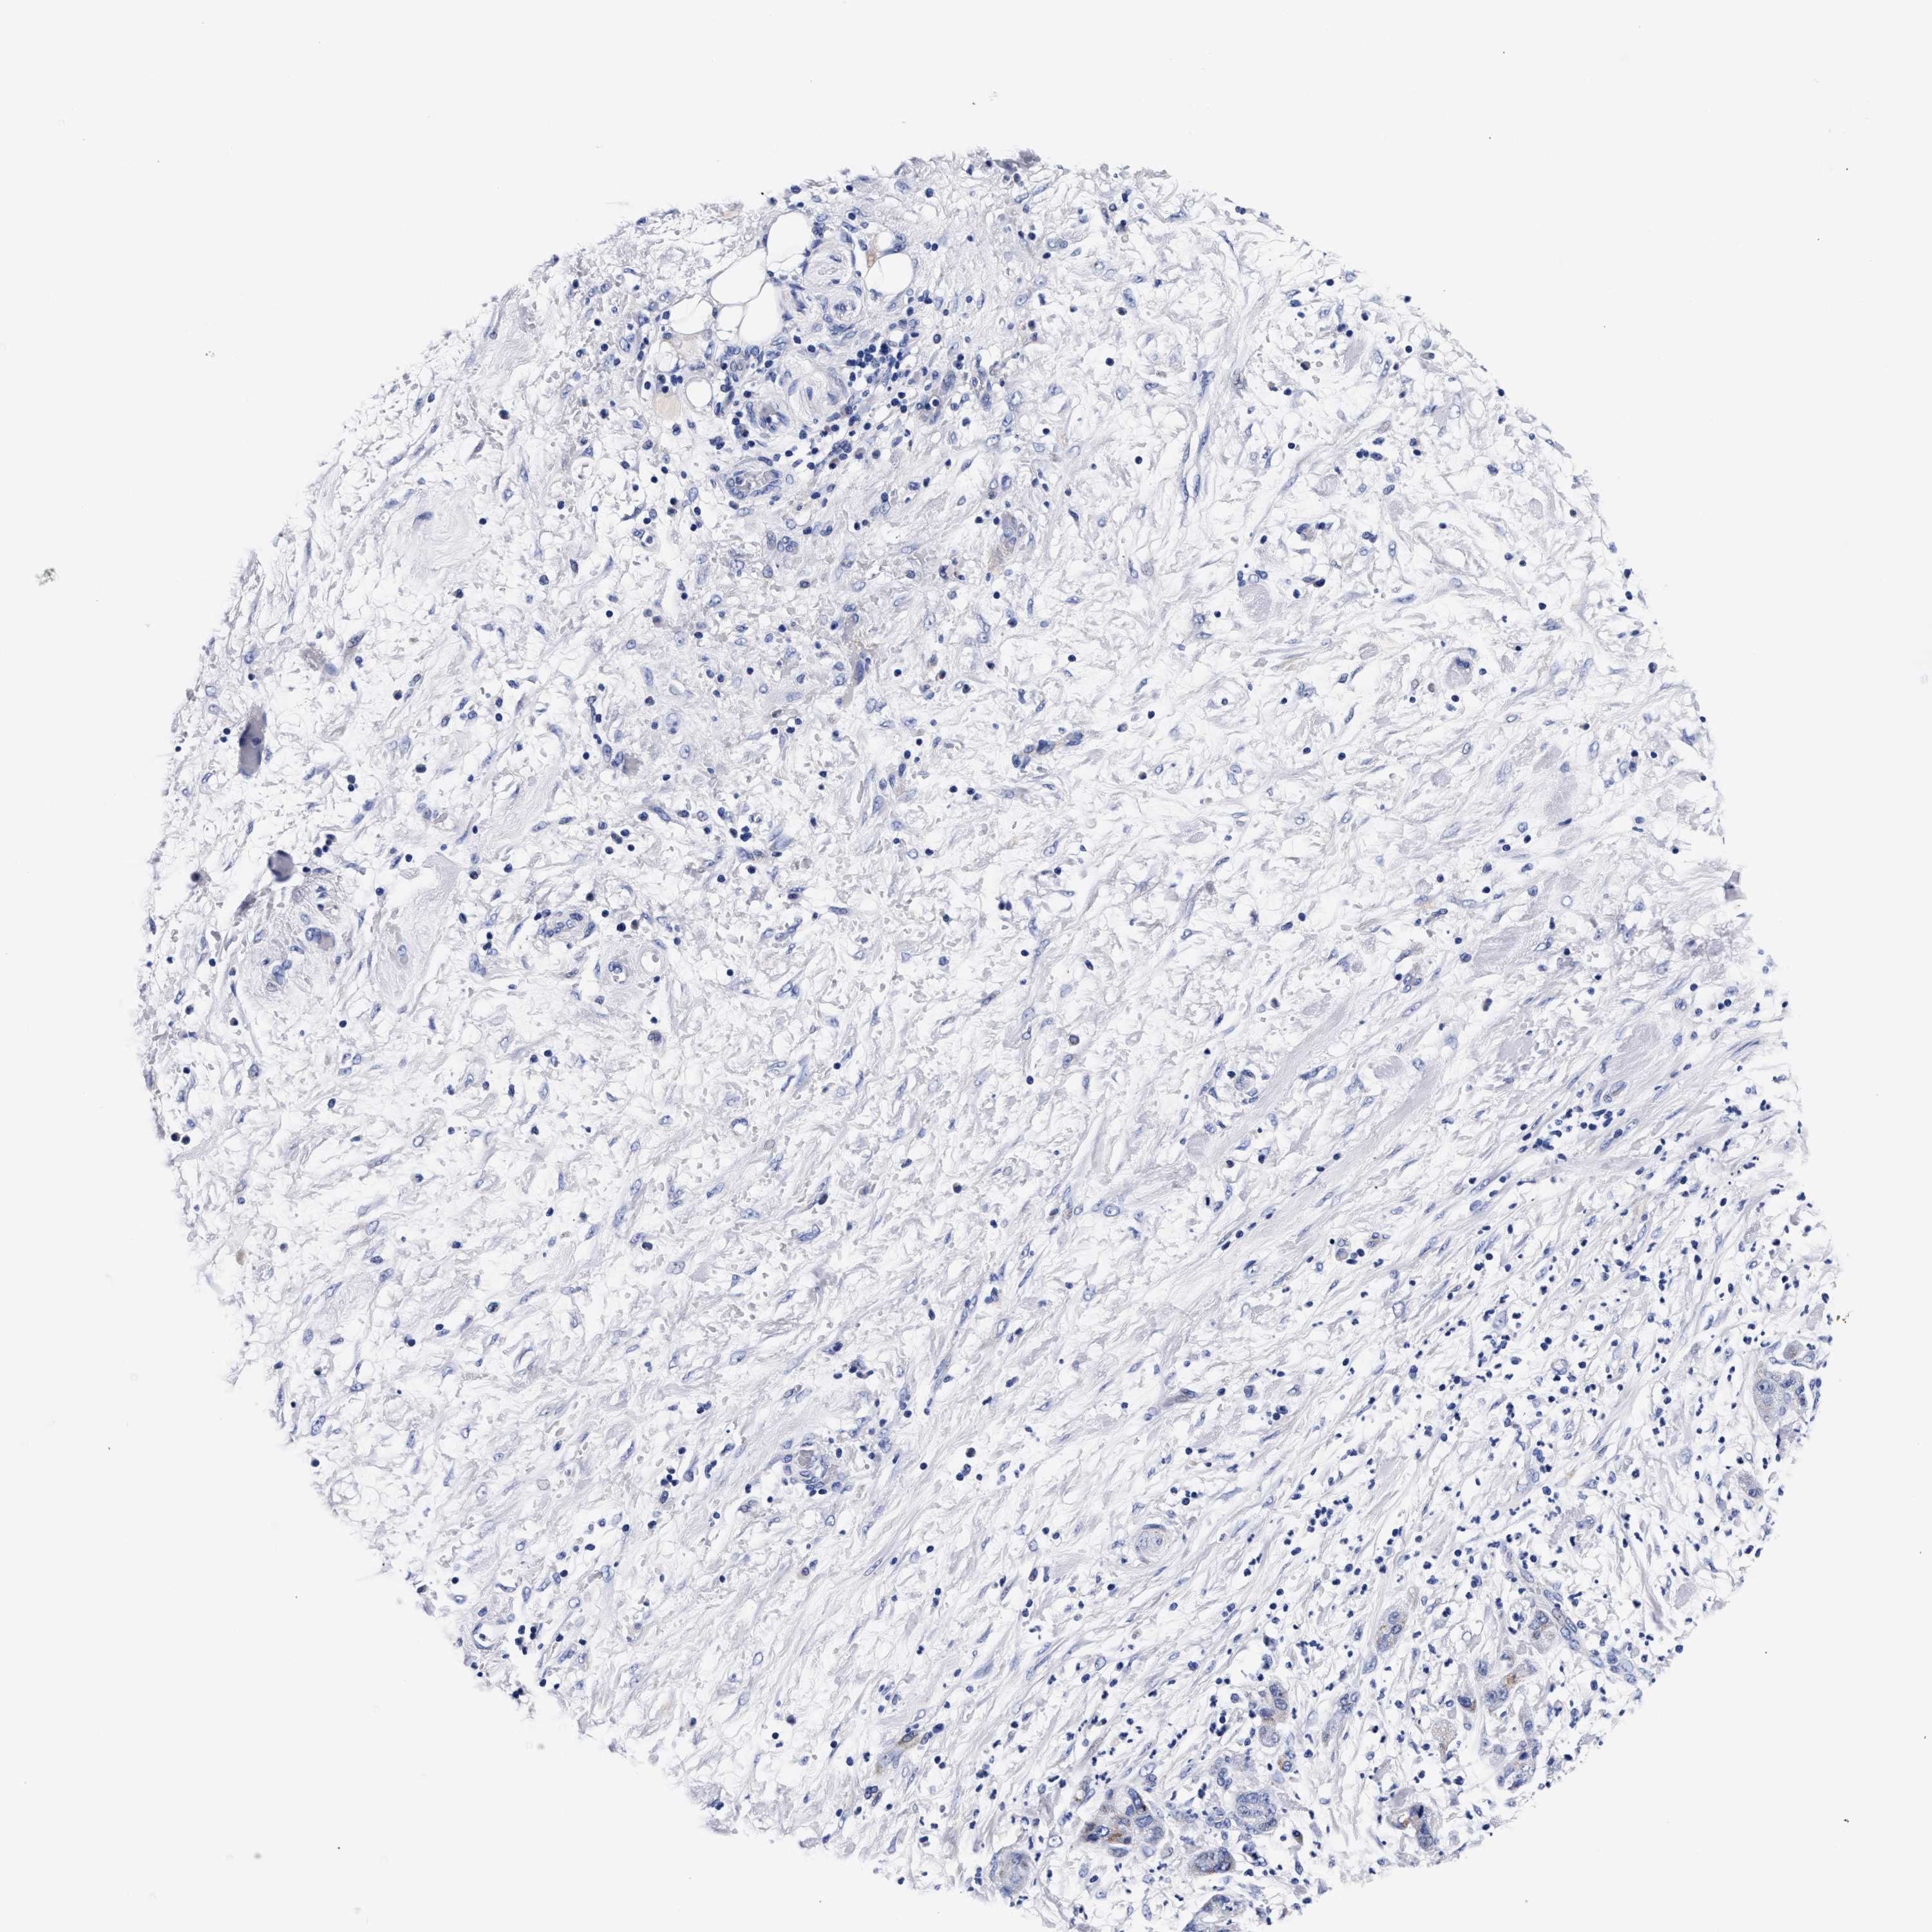

PANCREATIC CANCER - Protein expressioni

A mouse-over function shows sample information and annotation data. Click on an image to view it in a full screen mode. Samples can be filtered based on level of antibody staining by selecting one or several of the following categories: high, medium, low and not detected. The assay and annotation is described here.

Note that samples used for immunohistochemistry by the Human Protein Atlas do not correspond to samples in the TCGA dataset.

Antibody stainingi

Antibody staining in the annotated cell types in the current human tissue is reported as not detected, low, medium, or high, based on conventional immunohistochemistry profiling in selected tissues. This score is based on the combination of the staining intensity and fraction of stained cells.

Each image is clickable and will lead to virtual microscopy that enables deeper exploration of all samples and also displays staining intensity scores, fraction scores and subcellular localization as well as patient and tissue information for each sample.

Antibody HPA003159

Antibody CAB023293

Adenocarcinoma, NOS

Adenocarcinoma, metastatic, NOS